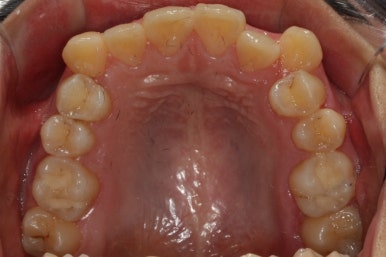

부산교정전문의 키다리아저씨치과에 처음 내원하셨을 때 당시의 입안 모습입니다.

윗니 뿐만 아니라 아랫니 부위에도 덧니가 관찰됩니다. 다른 앞니, 어금니 부위도 약간 삐뚤한 부분이 보입니다.